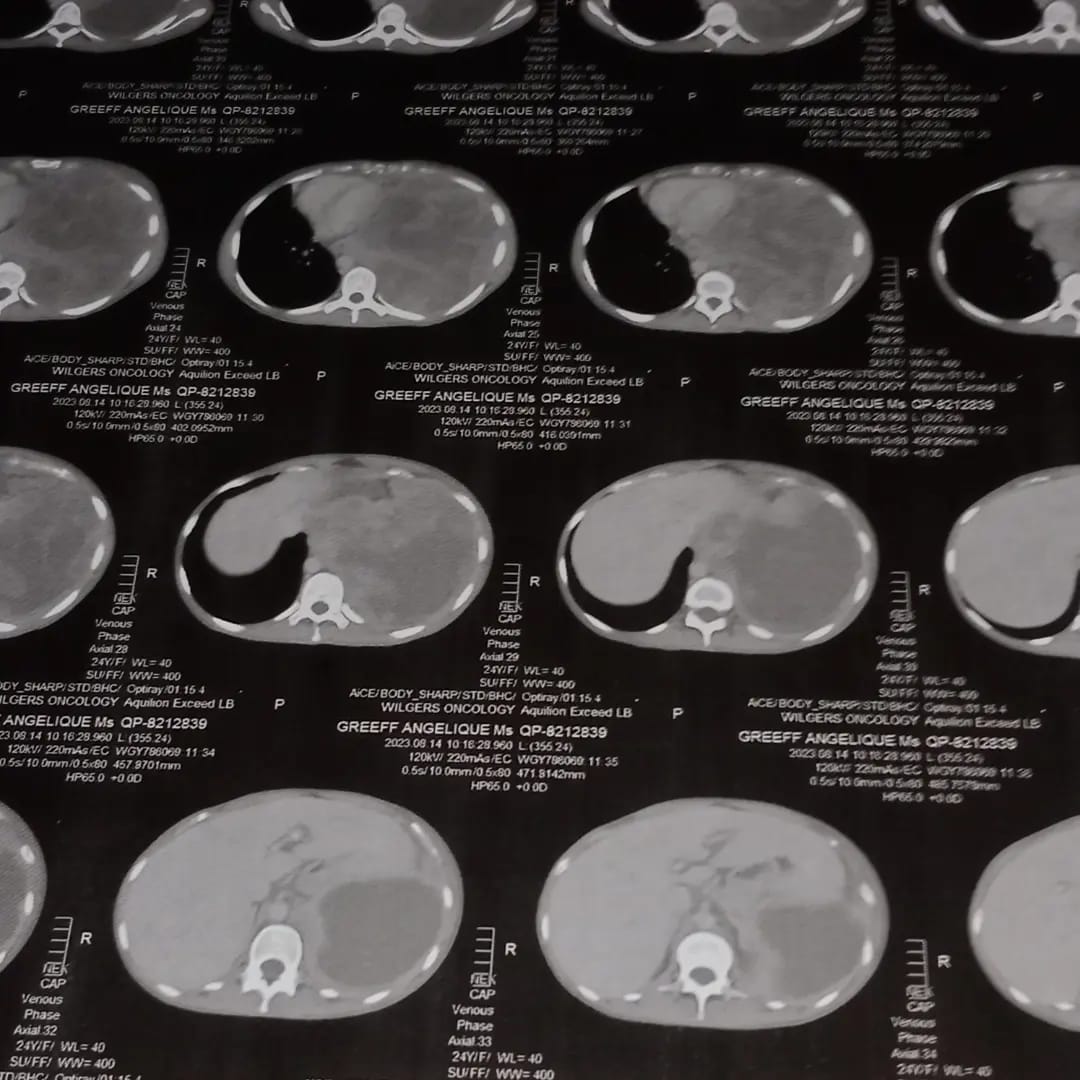

Angie oeh is gister (die 14de Augustus 2023) gediagnoseer met stage 4 longkanker. Hierdie is hectic. Sy kort dringend ‘n operasie as ‘n eerste stap om hierdie aaklige deel van haar lewe aan te pak voordat sy kan begin met behandeling vir chemoterapie.

Angie oeh is nie net aan die begin van haar loopbaan nie – sy is nog fokken jonk. Diê Afrikaanse kletsrymer is 24 jaar oud en sy is bitterlik bang. Sy het die volgende gepost op haar sosiale media platforms gisteraand.

“Vandag is ek gediagnosed met stage 4 long kanker. Eks bang. Eks so fokken bang. Elke keer as ek net ‘n klein tydtjie het om te dink huil ek soos n pussy. Hoe de fok gebeur so iets so vinnig sonder dat jy weet of dit voel?”

“Nou is ek so siek. Ek moet iemand vra om vir my n water bottle aan te gee wat reg langs my staan. Eks fokken 24. Ek moet ‘n life changing operation kry en na dit 6 maande se chemo. Ek het nie die emotional gemoed of die geld om die te doen nie. As enige iemand my kan help met iets wat R200 000 gaan kos asb, help my.”